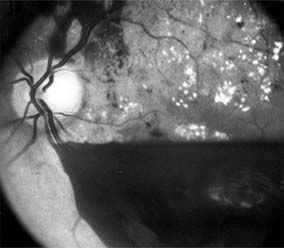

Figure 10-23

Figure 10-23: Fluorescein angiogram shows hypofluorescence from capillary drop-out (arrows) typical of ischemic diabetic maculopathy.